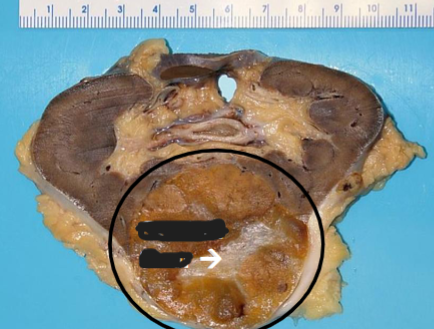

Angiomyolipoma

Benign, but if large may fatally hemorrhage

Neoplasm composed of: Vessels + Smooth muscle + Fat